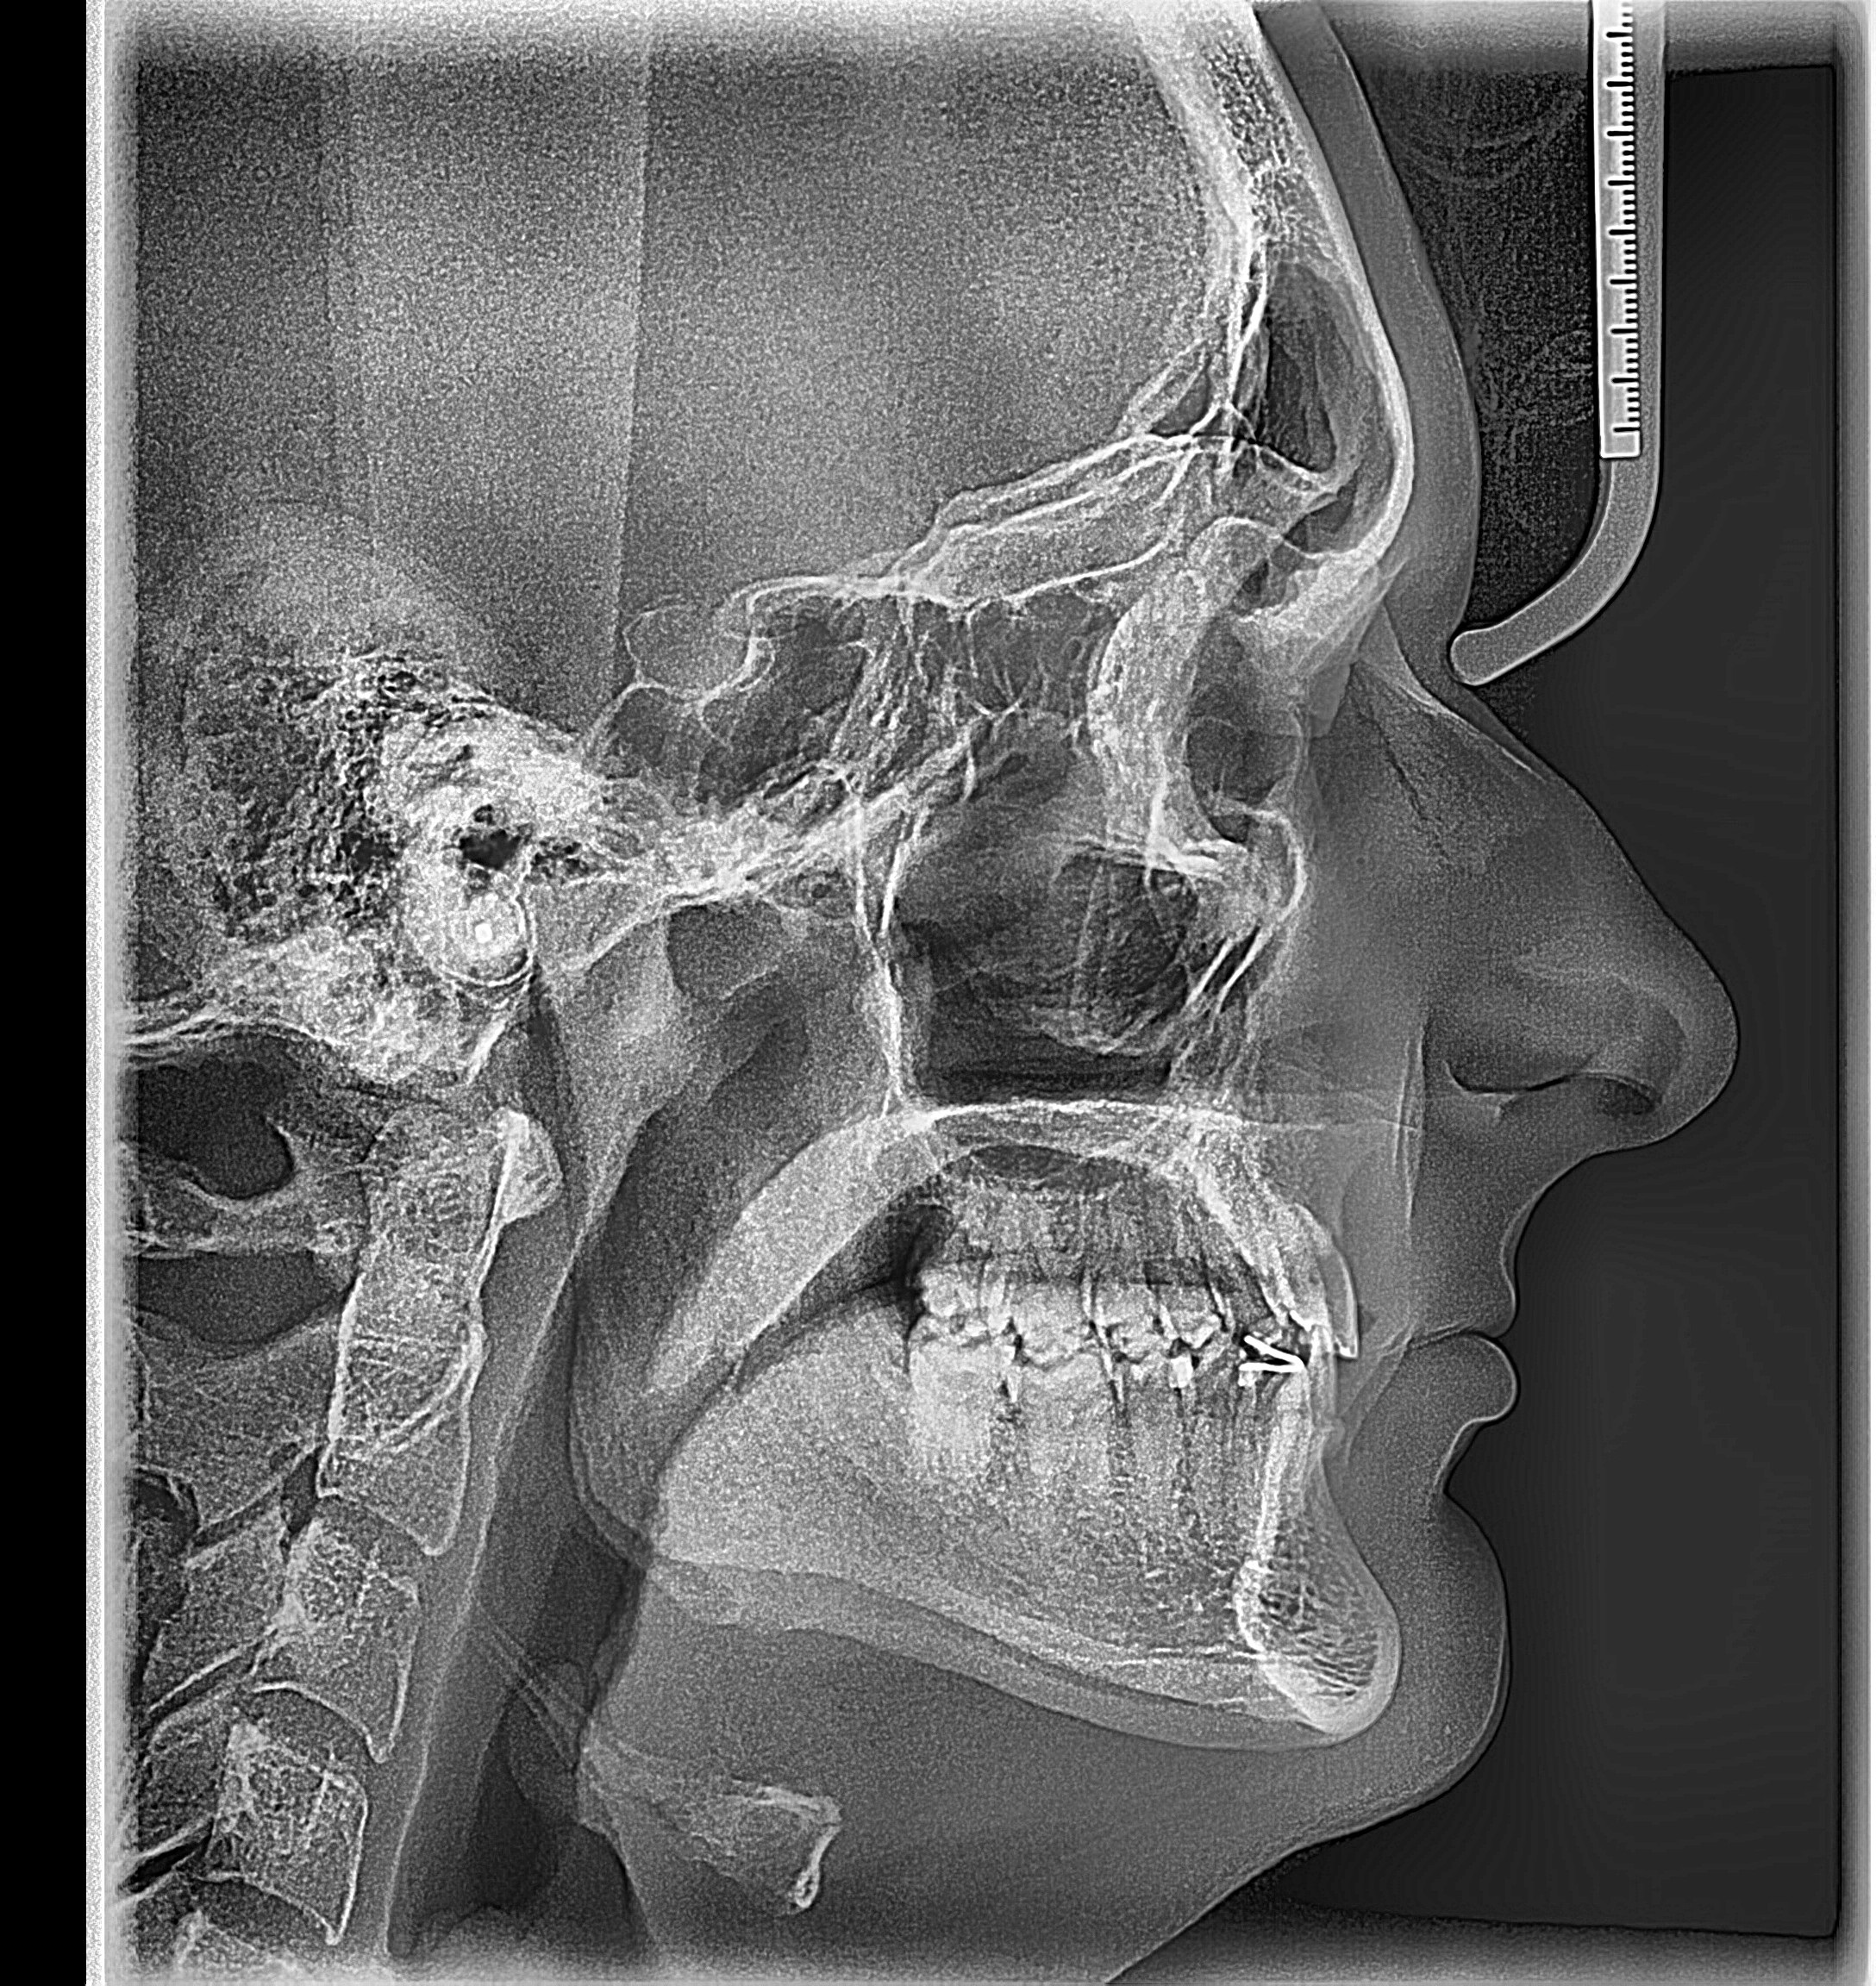

Any feedback about these procedures would be appreciated. I have attached my lateral ceph that he used to plan the jaw movements. It is pretty old and I have lost a lot of weight since then.

Any feedback about these procedures would be appreciated. I have attached my lateral ceph that he used to plan the jaw movements. It is pretty old and I have lost a lot of weight since then.